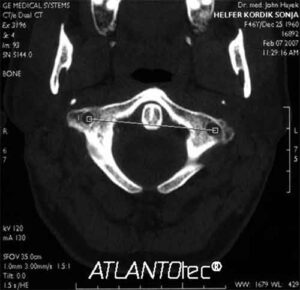

Secondo una ricerca Usa l'utilizzo della cosiddetta "Tac a spirale" riduce del 20% i casi di morte da tumore ai...